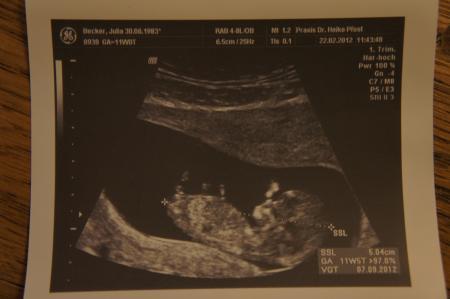

Hey ihr Lieben, wollte mich längst gemeldet haben und Euch meine 2 Bildchen vom FA Termin letzte Woche zeigen ;-) Die kleine, purzelbaumschlagende Maus zu sehen war einfach nur wunderschön... Alles schon dran, sogar die 10 winzigen Fingerchen - so goldig! Mein Freund war auch zum ersten Mal dabei und ist aus dem Staunen nicht mehr rausgekommen. Terminlich bin ich 9 Tage nach vorne gerutscht (neuer ET 03.09.). Ich bin unglaublich glücklich und inzwischen - da die kritische Zeit endlich vorbei ist - zum Glück auch etwas gelassener. Trotzdem sind natürlich nicht auf Knopfdruck alle Ängste wie weggewischt. Doch das gehört als werdende Mama wohl dazu ;-) Was meint ihr? Wünsche Euch einen schönen Kugeltag und grüße alle lieb, Julia

He, Dein Krümel rockt ja die Fruchthöhle Wir hatten hier schon einen Rebellen, eine Ulknudel und ne Schlafmütze. Jetzt also auch noch einen Rocker (hihi). Voll süß, man erkennt die Ärmchen ganz deutlich. Ein echt schönes Foto! LG Tina

Hallo Julia, hübsches Bild. Habt ihr eine Geschlechtsprognose bekommen? Ich finde, das sieht sehr eindeutig nach einem Jungen aus ;-) LG, auch Julia